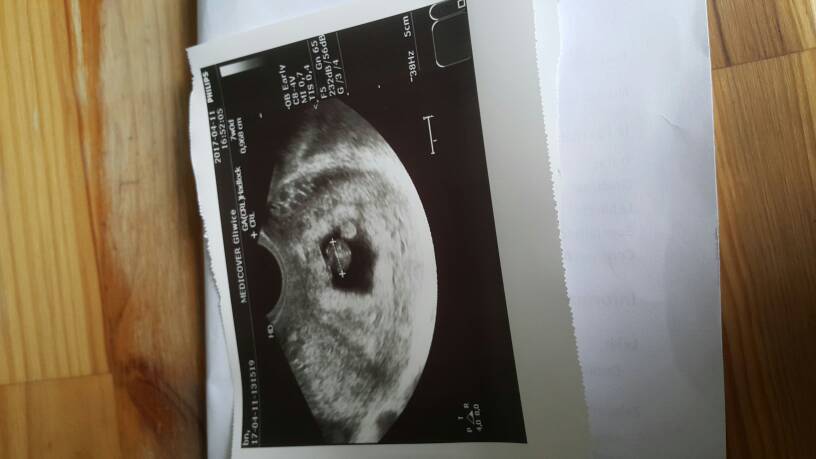

Millo cudownie!!!! Teraz już musi być dobrze :*Jestem przeszczesliwa!!Jestem w ciazy!!!Biło pieknie serduszko a pecherzyk sie zaokragli♡ Roznica 2 dni wedlug usg :*****Poplakalam sie tam)Niedowierzam!!happy happy happy!!!Jejku jestem szczesliwa!!Zobacz załącznik 802334